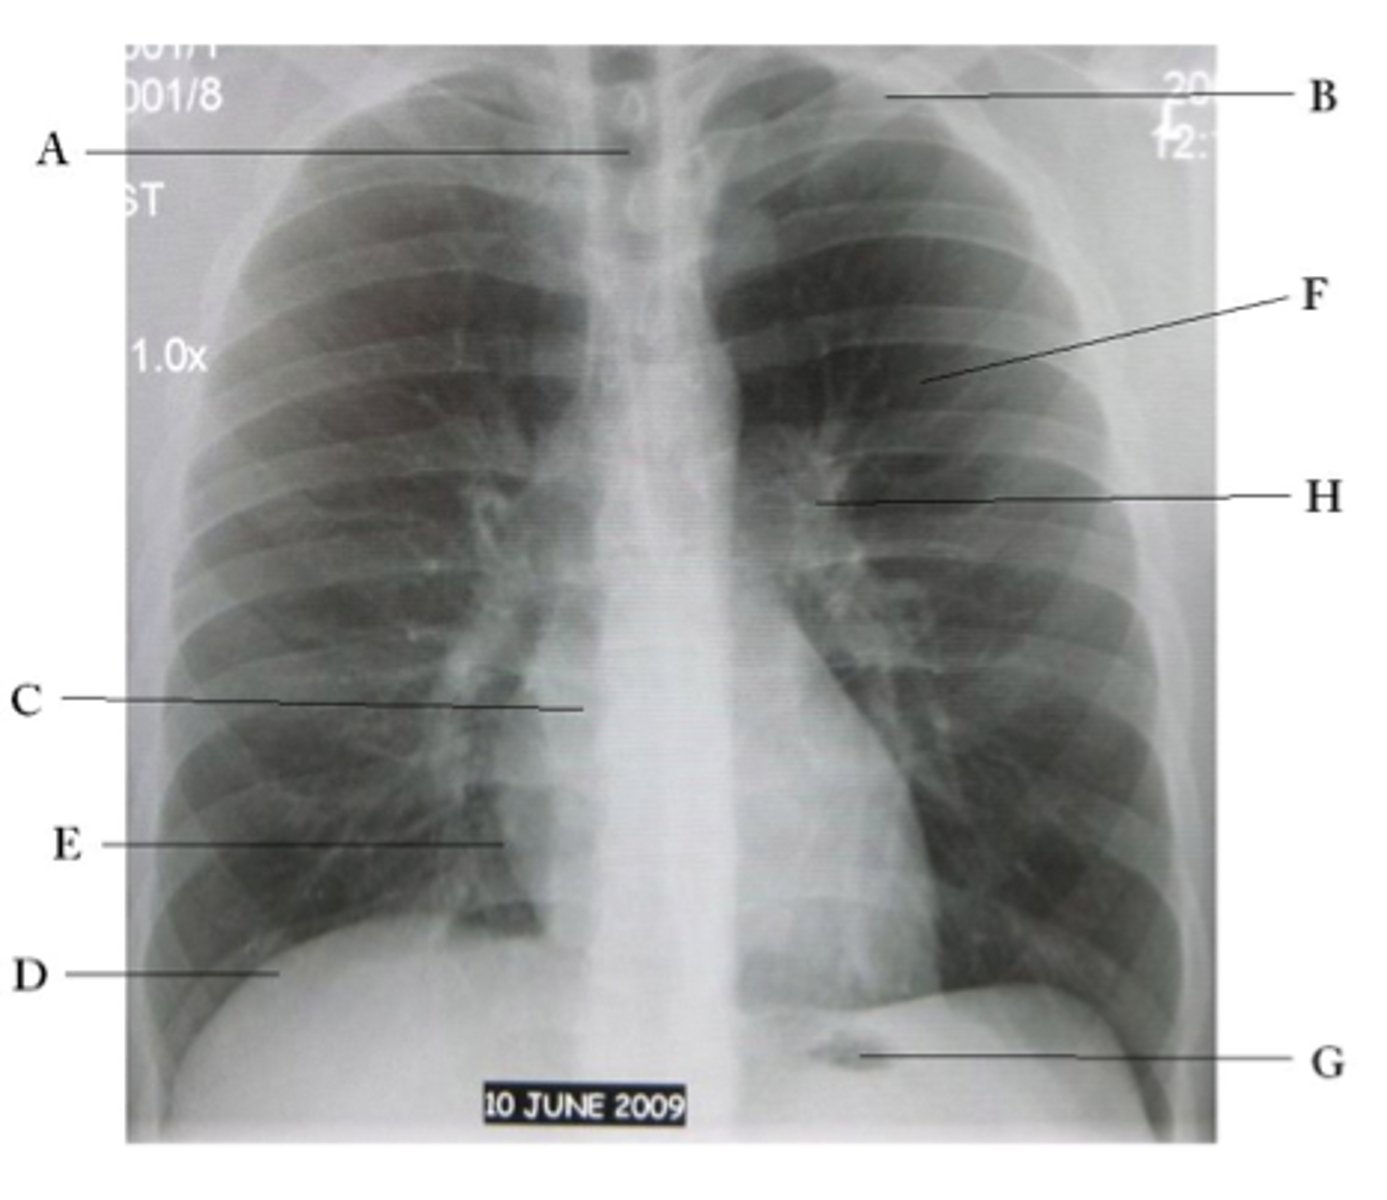

A

trachea

B

Clavicle

C

Right atrium

D

Diaphragm

E

Cardiophrenic angle

F

left upper lobe

G

gastric bubble

H

Left hilum